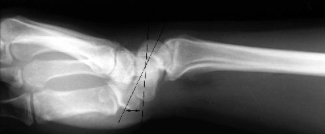

Lateral

AP